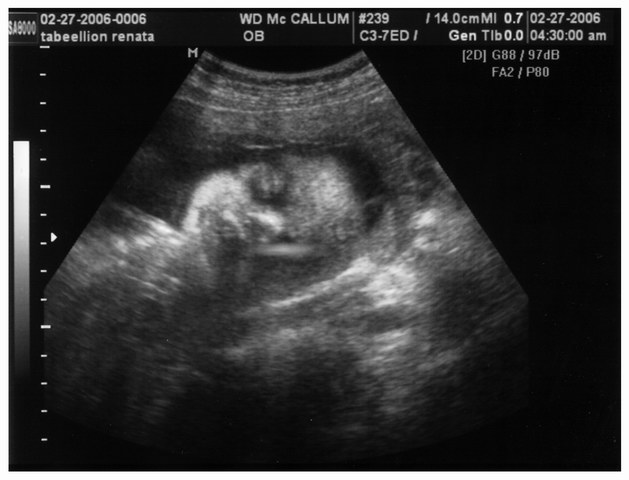

2/5 3/24/06 12:01 AM face2